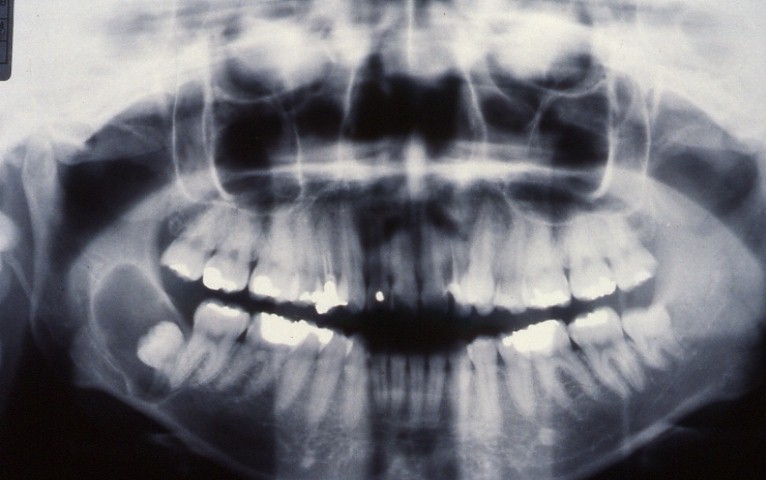

X線所見

顎嚢胞におけるX線検査は不可欠である。

X線的特徴としては、境界が比較的明瞭でX線不透過像を示す細い線状のいわゆる

cystic margineで囲まれたX線透過像として描写されます。

疾患の大きさ、形態、部位、辺縁の状態、歯との関係は診断のために重要な事項です。

疾患の解剖学的位置関係にはCTが、充実性腫瘍と嚢胞と鑑別には超音波エコーが便利です。